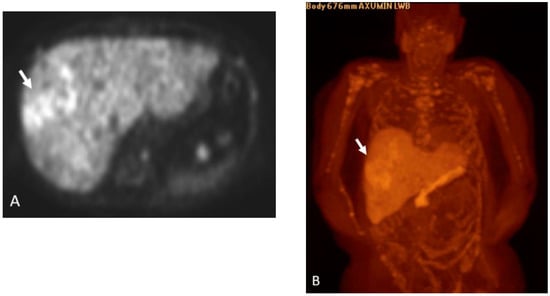

Detection of Loco-Regional Disease and Distant Metastases